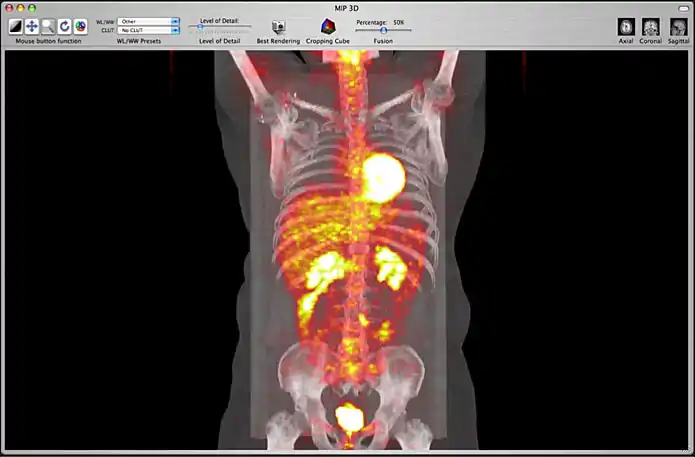

Image fusion is also available for 2D and 3D reconstructions implying that you can use image fusion along with MPR, Volume rendering, etc...

Image fusion in the 3D MIP window